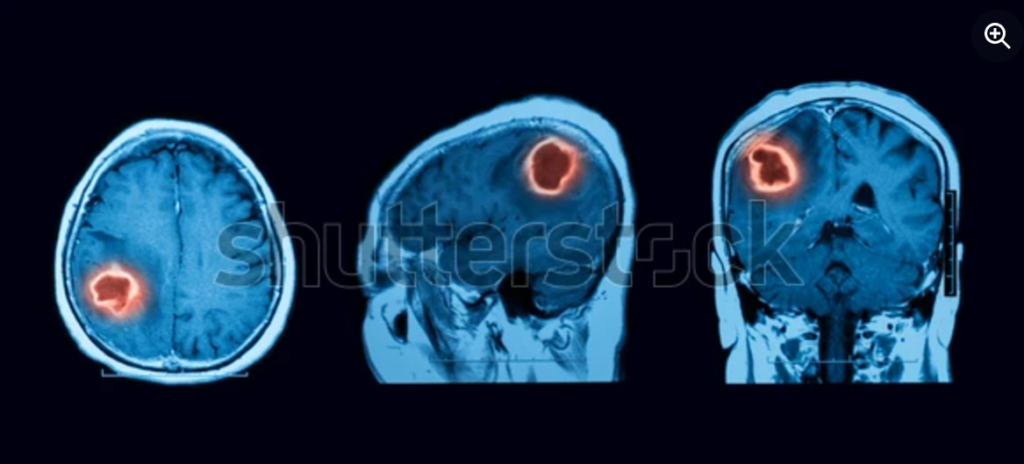

Chụp cộng hưởng từ hoặc chụp CT não : Chụp cộng hưởng từ (MRI) là xét nghiệm hình ảnh tốt nhất để xác định các khối u não. Chụp cắt lớp vi tính (CT) là một lựa chọn thay thế tốt nếu bạn không thể chụp MRI. Các xét nghiệm này có thể cho thấy kích thước và vị trí chính xác của khối u, và xác định liệu khối u có lan rộng sang các bộ phận khác hay không.

Chụp cộng hưởng từ (MRI) là xét nghiệm hình ảnh tốt nhất để xác định các khối u não